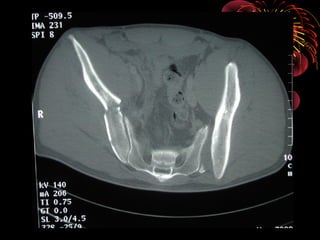

• TAC : Herramienta de elección en fx. de pelvis

permite evaluar el compromiso óseo, fragmentario,

grados de desplazamiento, compromisos

abdominopélvicos y diferenciar hematomas retro e

intra abdominales

TAC AXIAL DE PELVIS

TAC HELICOIDAL AXIAL

RADIOLOGÍA • LA IMAGENOLOGIANO DEBE RETRASAR MANEJO INICIAL • TIPO DE IMÁGENES ESTA DADO POR MECANISMO, GRAVEDAD Y CAPACIDAD DEL CENTRO • PARTIR DE UNA RX. A.P. PARA DIAGNÓSTICO • COMPLEMENTARIS : 60°”E”-30°”S” Y OBLICUAS • TAC : Herramienta de elección en fx. de pelvis permite evaluar el compromiso óseo, fragmentario, grados de desplazamiento, compromisos abdominopélvicos y diferenciar hematomas retro e intra abdominales • Uretrocistograma en caso de hematuria franca • Angiografía :evidencia de hematom retroperitoneal y perdida de mas de 4 unidades de GR